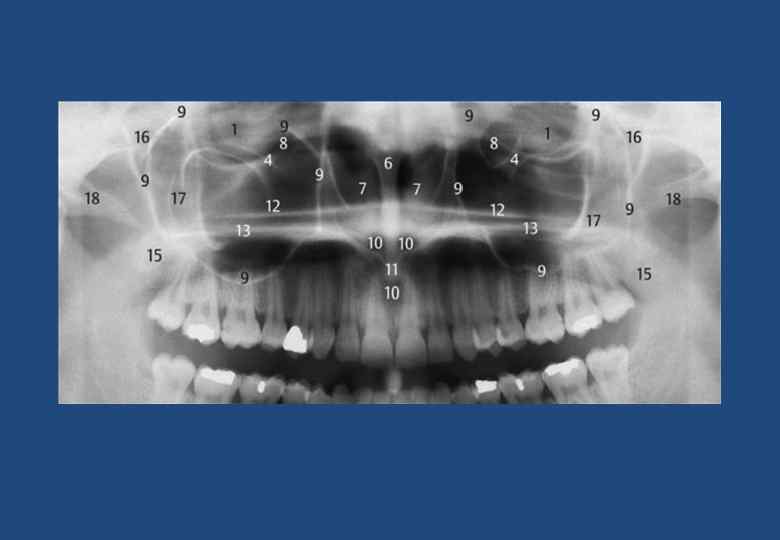

• 1. Рентгенанатомия при ОПТГ. • 2. Глазница • 3. Атлантоокципитальное сочленение • 4. Щека с носогубной складкой • 5. Подглазничный канал • 6. Компактное вещество в основании противоположной стороны челюсти • 7. Перегородка носа с носовым гребнем верхней челюсти • 8. Нижняя носовая раковина • 9. Слезная ямка • 10. Верхнечелюстная пазуха (границы) • 11. Носонебный канал и резцовое отверстие • 12. Верхняя носовая ость • 13. Горизонтальная пластинка небной кости • 14. Латеробазальная граница носовой полости, крыша неба располагается между 12 и 13 • 15. Спинка языка • 16. Небная занавеска • 17. Крыловидно-небная ямка • 18. Тело скуловой кости с безымянной линией • 19. Скуловая дуга